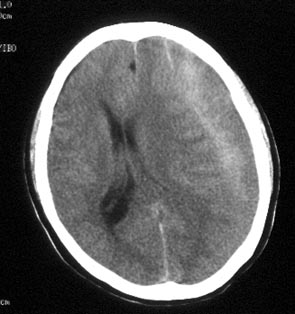

病史:男性,56岁,自觉右侧肢体肌力下降,伴麻木不适半月,逐渐加重。一个月前曾有头部轻微碰伤史,但具体经过不能回忆。

ct平扫:左额及颞顶叶见新月形略高密度血肿影,左右及前后径为2.5x12.7cm。左侧脑室受压变形右移,中线右偏约1.2cm,且密度增高,鞍上池闭塞,中脑受压变形。

ct诊断:左额、颞、顶部慢性硬膜下。